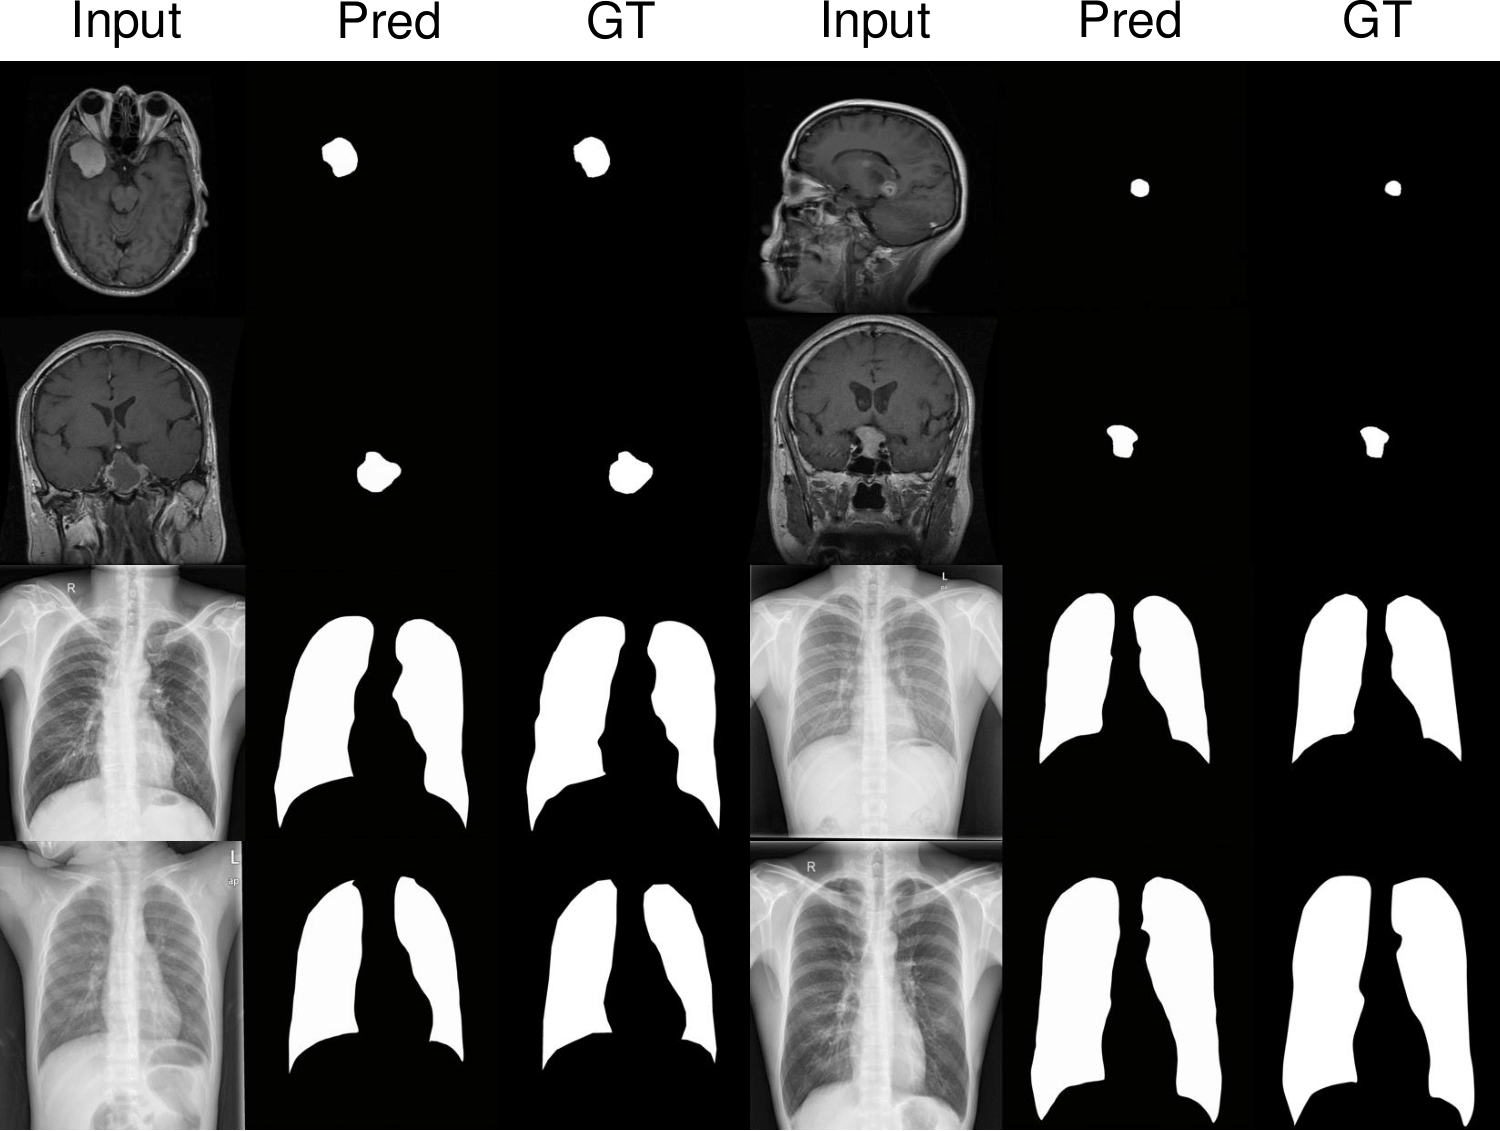

2. 의료 영상 분석

- X-ray, CT 스캔 등의 의료 영상에서 병변 감지 및 분할 수행

- 데이터가 적은 의료 영상에서도 Zero-shot 학습 가능